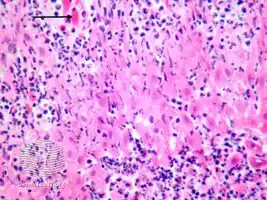

Infected keratocytes in skin swell and die.[2] The stain Lendrum’s phloxine tartazine, may be used to identify farmyard pox inclusion bodies.[2] Other tests include culture, fluorescent antibody test and electron microscopy.[2]

Cowpox, horsepox and smallpox may look similar and the histology may appear the same.[2]